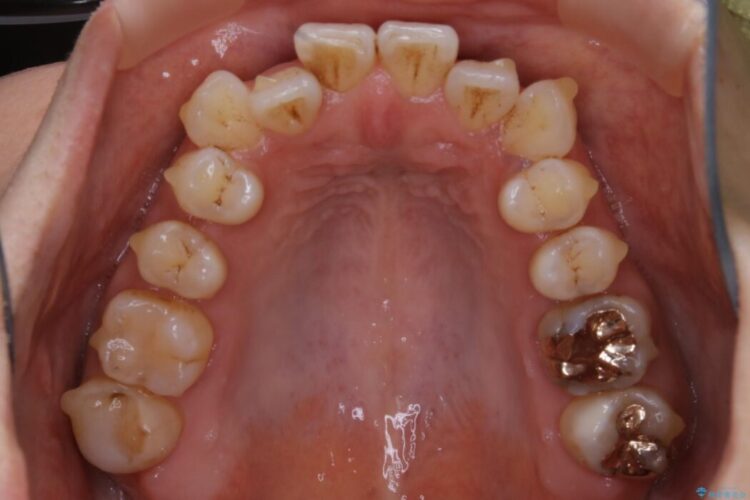

治療後について

きちんと装着時間を守っていただいたこともあり、きれいな歯並びを獲得できました。

マウスピースとマイクロインプラントの併用により矯正するための隙間を確保し、治療期間は長くなりますが非抜歯できれいな歯列弓を得ることができます。